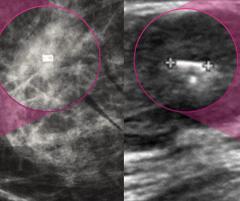

Current Perspectives on Digital Breast Tomosynthesis in Women with Dense Breasts

In what may be the largest study to assess digital breast tomosynthesis (DBT) screening of women with dense breasts, researchers noted only a 61.8 percent sensitivity for women with extremely dense breasts.